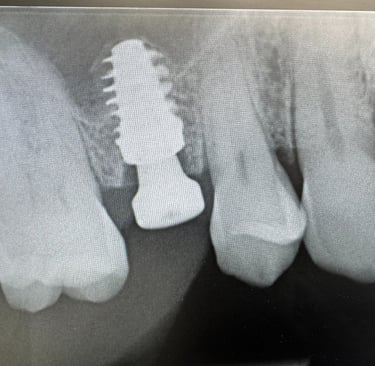

Hammasimplantti on titaaninen tai keraaminen 'ruuvi' joka asetetaan luuhun. Tämän varaan voidaan valmistaa yksilöllinen hammas.

Yleensä paraneminen kestää muutaman päivän. Urheilua ei suositella parin seuraavan päivän aikana leikkauksesta. Kokonaisuudessaan implantti on 8-12vk kohdalla täysin luutunut ja lopullinen hammas voidaan valmistaa.

Mielestäni kyllä. Ja siksi käytän vain Straumann -implantteja. Niiden avulla saadaan paras mahdollinen rakenne ennustettavalla luutumisella. Myös tärkeää on että tulevaisuudessa on osia tarvittaessa saatavana. Maailmassa on noin 600 eri implanttimerkkiä käytössä ja olen valinnut Straumann implantit juuri näistä syistä. Straumann implantit on olleet kymmeniä vuosia markkinoilla ja tutkimus niiden osalta on perusteellista.